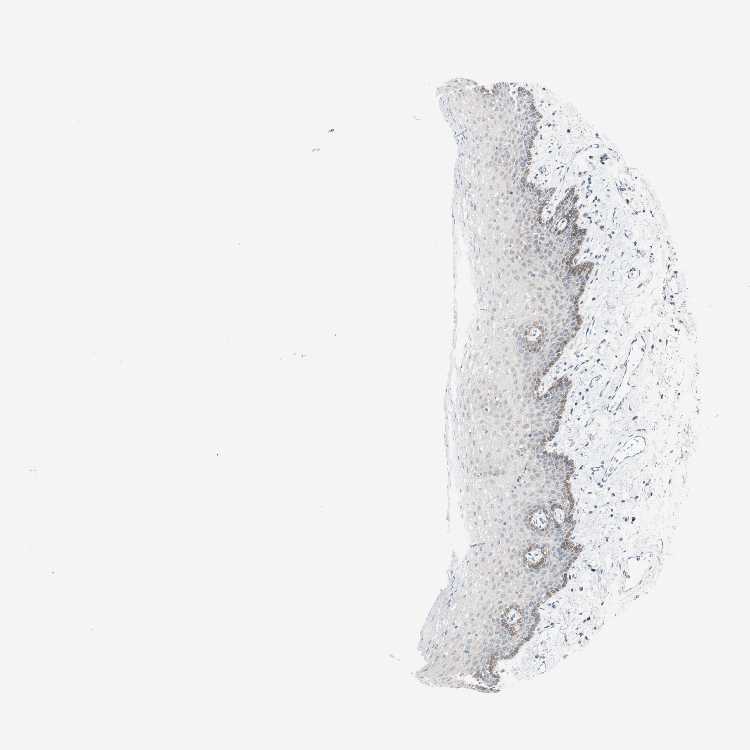

TISSUE PRIMARY DATA ORAL MUCOSA Show tissue menu

ORAL MUCOSA - Antibody stainingi

Antibody staining in the annotated cell types in the current human tissue is reported as not detected, low, medium, or high, based on conventional immunohistochemistry profiling in selected tissues. This score is based on the combination of the staining intensity and fraction of stained cells.

Each image is clickable and will lead to virtual microscopy that enables deeper exploration of all samples and also displays staining intensity scores, fraction scores and subcellular localization as well as patient and tissue information for each sample.

Antibody HPA021989Antibody HPA027838

Squamous epithelial cells LowMedium